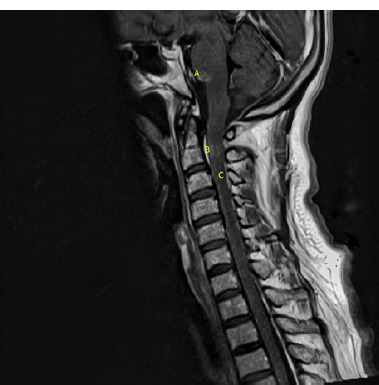

Case description: A 51-year-old woman presented with persistent holocranial headache, nausea, vertigo, and neurological deficits one month after a COVID-19 hospitalization. Neurological examination revealed hemiparesis, dysphagia, and ataxia. Imaging showed lesions in the central nervous system. A diagnosis of neurosarcoidosis was considered, supported by clinical criteria, imaging findings, and elevated ACE levels. Steroid therapy led to symptom improvement.